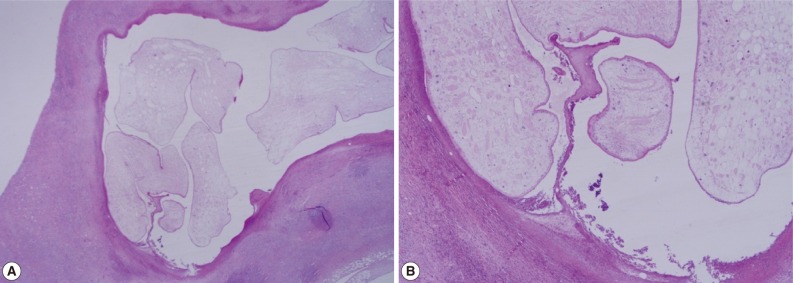

A 56-year old male visited our out-patient clinic for pancytopenia. Bone marrow biopsy and karyotype analysis showed myelodysplastic feature with 14% blast count and normal karyotype, indicating MDS, refractory anemia with excessive blast. He received 4 cycles of decitabine treatment during searching for matched unrelated donor, and partial response was shown. Allogeneic peripheral HSCT with myeloablative conditioning regimen consisting of busulphan and cyclophosphamide was performed from a HLA full-matched unrelated donor. However, at day 5 post-HSCT, 5 cm-sized hard and movable mass in the left scrotum and multiple palpable lymph nodes was detected at the left inguinal area. Pelvic magnetic resonance imaging and computed tomography were done and it was suspected initially as a myeloid sarcoma in the subcutaneous fat layer of the left scrotum and pathologic lymphadenopathy at the left inguinal area (Fig. 1). In order to confirm the diagnosis, gun biopsy was done on the left scrotal mass to avoid bleeding due to thrombocytopenia after HSCT. The result of the gun biopsy was inflamation of fibrovascular soft tissues with extensive interstitial eosinophilic infiltrations without evidence of malignancy. Persistent peripheral eosinophilia was also developed after HSCT. Subsequently, IgG antibody tests for paragonimiasis, cysticercosis, sparganosis, and clonorchiasis were done, and the results were positive for sparganosis and negative for all others. We re-evaluated the patient's past history and found out that he had swam in the river and ate raw fish, cow liver, and pork meat frequently when he was young. For a next step, excision biopsy was done as an approach for therapeutic diagnosis after recovery of thrombocytopenia. The cut surface of the biopsied specimen showed a cyst filled with whitish and myxoid tissues, measuring 2.0×0.6 cm (Fig. 2). The biopsy result was severe acute and chronic inflammation and fibrosis with a sparganum worm (Fig. 3). He was discharged after complete wound healing and stabilization of the post-HSCT condition.

Most sparganosis cases present as lumps in subcutaneous tissues or intermuscular fascia, which are non-tender and sometimes resolve spontaneously. Therefore, the diagnosis is often made incidentally by an imaging study or surgical biopsy in many cases. Because of late diagnosis, the sparganum worm is presumed to have lived many years, and even a 10-year survived sparganum was reported [9]. The final diagnosis is done by the surgical biopsy proving the presence of the worm. However, immunodiagnosis is also recommended to establish a preoperative diagnosis when soft tissue tumors are detected in patients living in endemic areas [3].